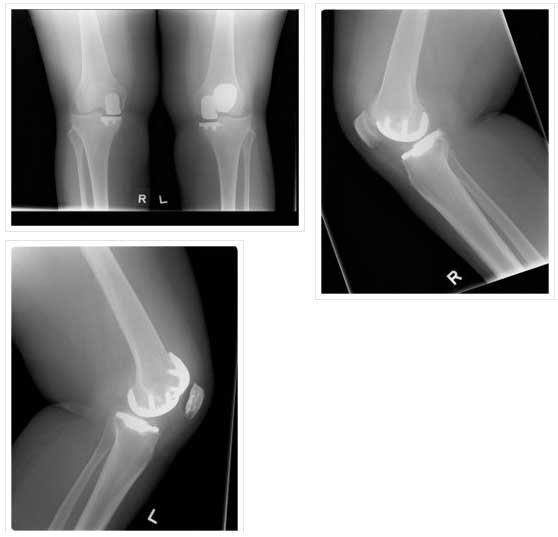

BILATERAL PATELLOFEMORAL REPLACEMENT

BILATERAL PATELLOFEMORAL REPLACEMENT

LATERAL VIEW